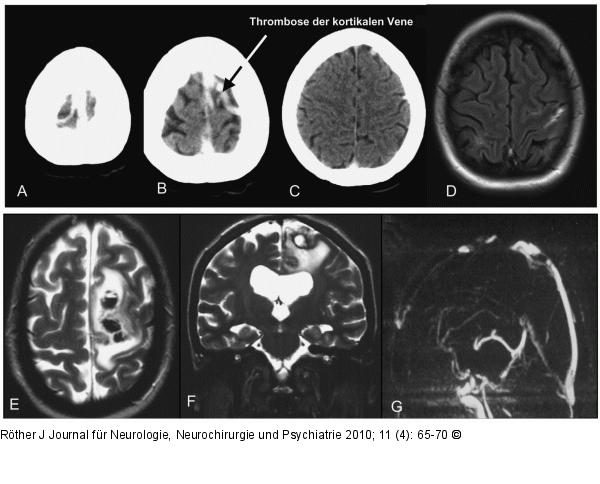

Abbildung 1: SVT Bildgebung der SVT: Thrombose des Sinus sagittalis superior und der V. Rolandi. Klinisch zunächst nur Kopfschmerzen bei intrakranieller Hypertension, im Verlauf fokal-motorische Anfälle und beinbetonte Hemiparese rechts nach Entwicklung des Stauungsinfarkts mit Stauungsblutung. A–C: CT mit hyperdensem Sinus sagittalis superior und einer kortikalen Vene; D: MRT (FLAIR) mit einer kortikalen Venenthrombose; E, F: MRT (T2w) Stauungsblutung hochfrontal links; G: MR-Venographie mit Thrombose des Sinus sagittalis superior. |

Bildgebung der SVT: Thrombose des Sinus sagittalis superior und der V. Rolandi. Klinisch zunächst nur Kopfschmerzen bei intrakranieller Hypertension, im Verlauf fokal-motorische Anfälle und beinbetonte Hemiparese rechts nach Entwicklung des Stauungsinfarkts mit Stauungsblutung. A–C: CT mit hyperdensem Sinus sagittalis superior und einer kortikalen Vene; D: MRT (FLAIR) mit einer kortikalen Venenthrombose; E, F: MRT (T2w) Stauungsblutung hochfrontal links; G: MR-Venographie mit Thrombose des Sinus sagittalis superior. |